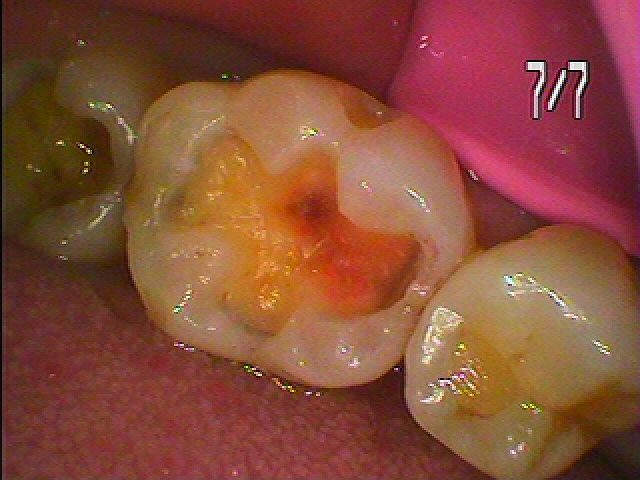

虫歯が出てきました

かなり深部にまで年月とともに進行していました

虫歯を除去してCR樹脂にて覆罩を行っています